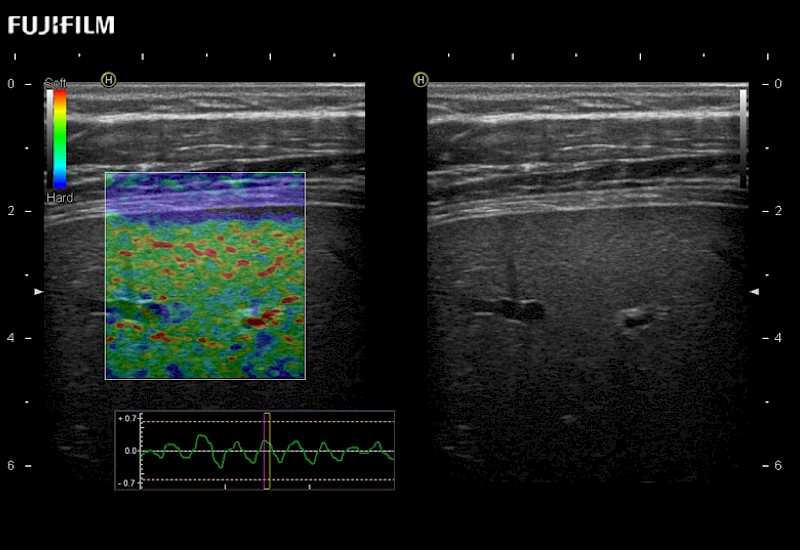

Multi-Parametric imaging modalities

Extraordinary high-resolution digital imaging

The ARIETTA 750 incorporates all of the proven technologies and functions that medical professionals have come to expect from Fujifilm Healthcare.

ARIETTA 750 is the definitive diagnostic ultrasound solution for any clinical setting - Private Office, Imaging Center, or Hospital. The ARIETTA platform provides the ultimate in clinical performance with its state-of-the-art features and large user-friendly display.

The ARIETTA 650 DI combines trusted Fujifilm Healthcare technologies and features tailored for surgical oncology.

Designed to meet the demands of surgeons, the ARIETTA 650 DI offers precise guidance. Its advanced capabilities and large, intuitive display offer accurate and efficient care in operating rooms and specialized surgical settings.